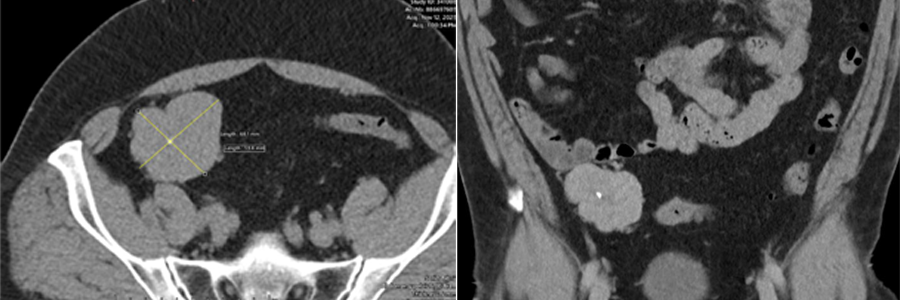

Caso 1 | Abril 2026 | Hospital Italiano 45 años. Masculino. MC: dolor inguinal derecho con irradiación a testículo de dos días de evolución.